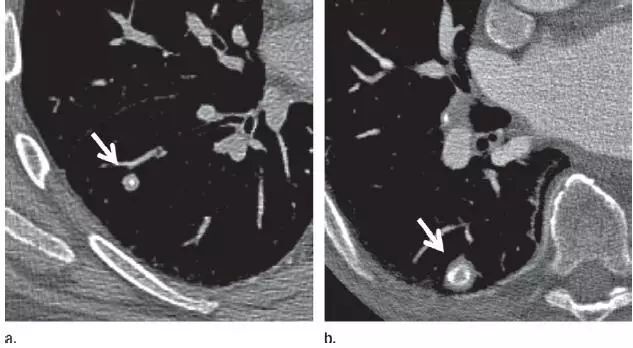

2. 肉芽肿

图 2 CT 图像显示边界清楚的中心钙化(a)或层状钙化(b)结节,均为典型的肉芽肿表现。不建议进一步 CT 随访。